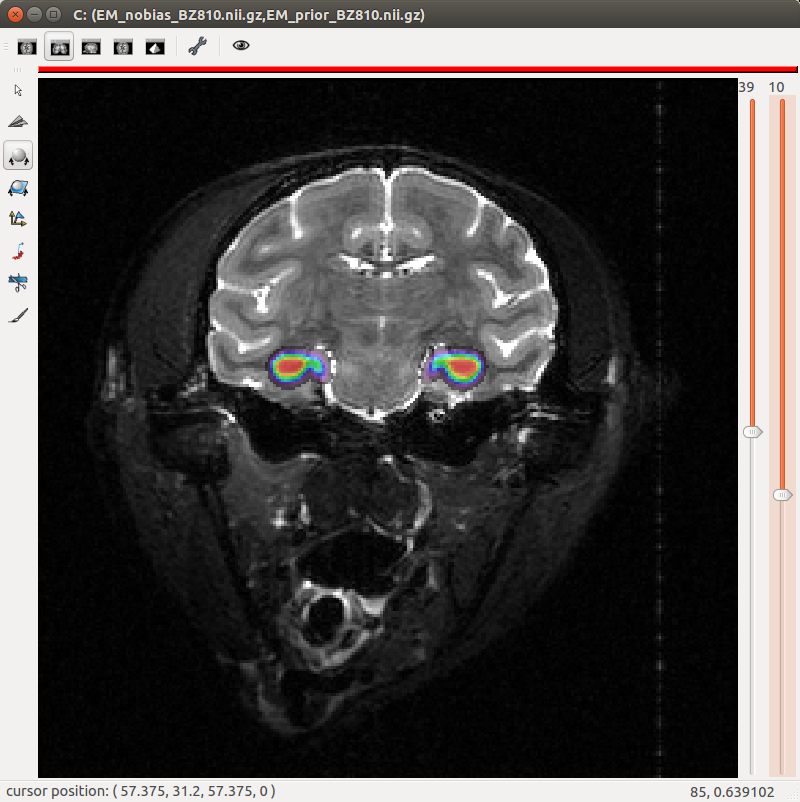

Prior probabilities are stored in a 4D volume with indices in the 4 dimension corresponding to class labels. Labels should thus be consecutives and start at 0.

Figure 5. "Eye" visualization of the prior probabilities for classes "isocortex", "white matter" and "dorsal pallium".